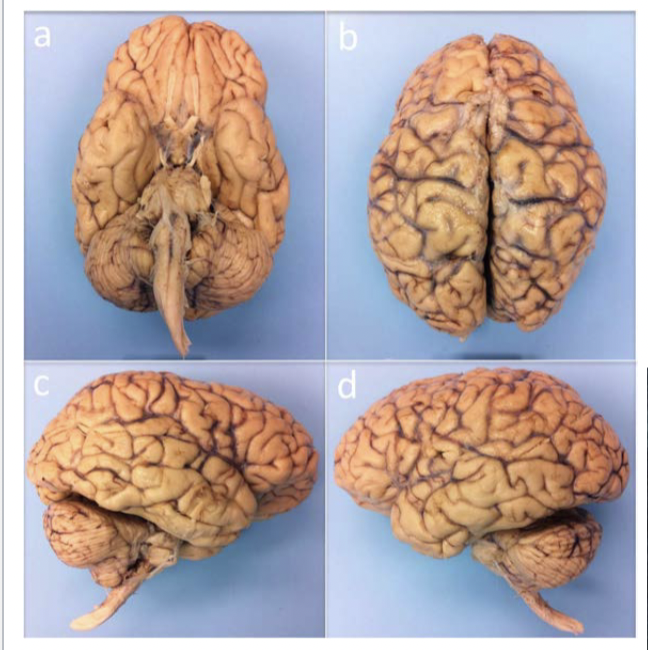

Why have different views of the brain

A

Different views = show you different things

Example - cornal = see deep matter structures (Ex. see basal ganglia)

***Applies to reading scans - need to pay attention to the view of the scan

12

Q

A - Ventral view - can see brainstem

B - BIG line in middle = central sulcus (seperates the two hemispheres)

- Can also see sinus

C - se the cerebelum